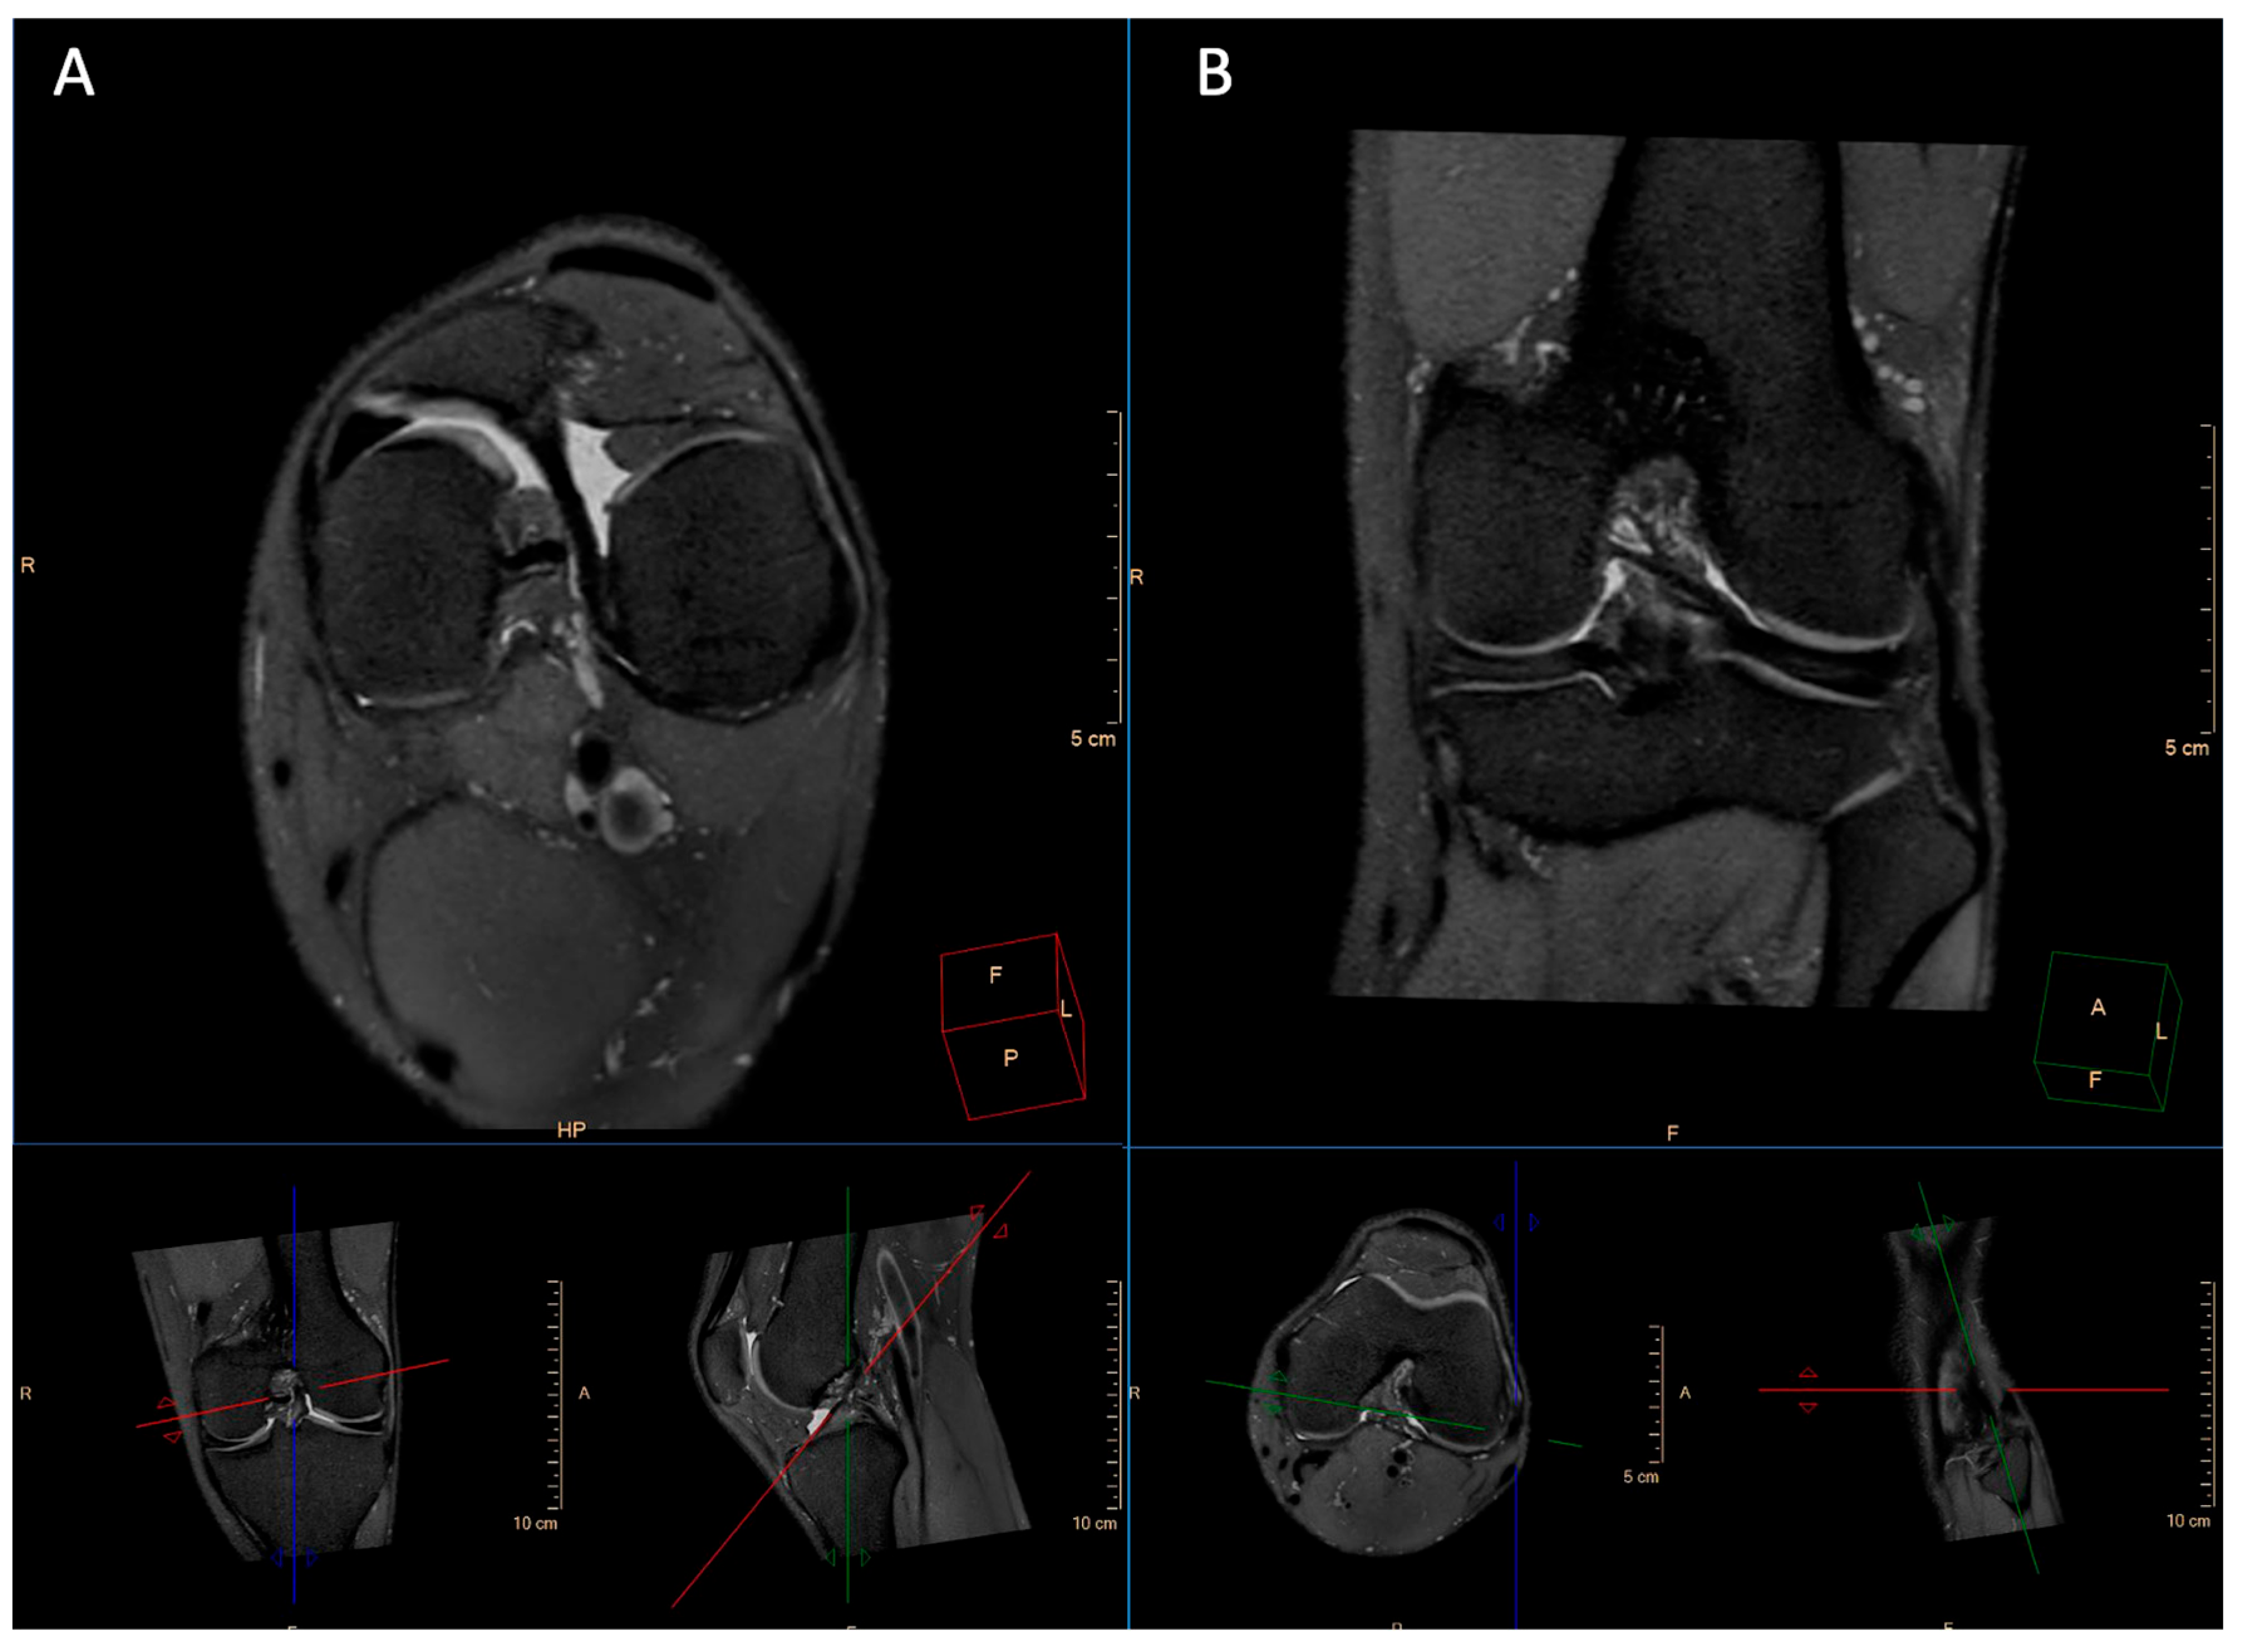

2.2. Imaging Technique

3.1. Image Quality

3.2. Artifacts

4. Discussion